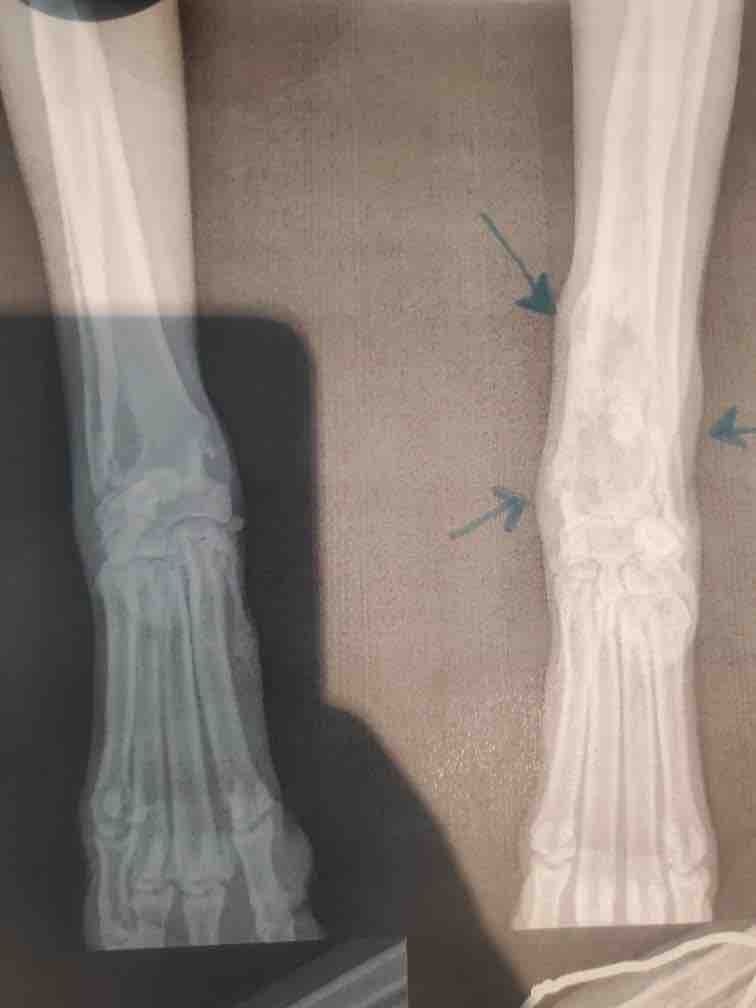

Hi, My name is Brianna and just 2 days before Thanksgiving my family received terrible news we were far from ready for. Our family dog whom we love so much and have had since she was only 4 months was diagnosed with Osteosarcoma aka bone cancer. This is an aggressive cancer accompanied by painful bone destruction where it grows. The treatment for this cancer is limited and our only option to give Cleo a fighting chance is to amputate Cleo's front left leg and follow up with chemotherapy and immunotherapy. All of this is in hopes to extend Cleo's life as well as improve the quality of her life being she is currently in pain and limping due to the cancer in her leg. Unfortunately, all these treatments will be very expensive as Cleo does not have pet insurance. I am starting this Go Fund Me in order to help my family with costs as this diagnosis has taken us by surprise and we were unable to prepare for this terrible diagnosis. Currently we only have an estimate for Cleos amputation which all funds will be going towards. Additional funds will be going towards her chemotherapy, immunotherapy, and any additional treatment.